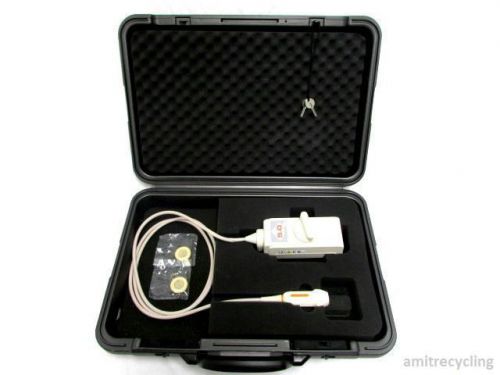

Aloka Phased Array 5 MHz UST-5267-5 Kardio Ultrasound Probe w/Case "Must See" !$